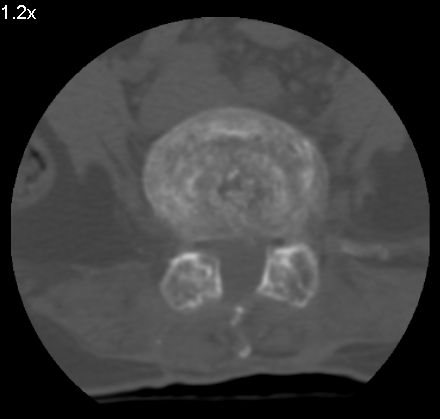

以下是引用余辉在2007-9-4 21:00:00的发言:[br]椎体棘突有点异常(像是被切割了),不知有否手术史,如椎体融合术等。单纯的退行性变可以出现椎间隙变窄,但同时一般会出现椎体上下缘的硬化增生,且椎体间完全融合的机率更小,本例椎体完全融合且椎体上下皮质缘破坏掉了,如果没有手术史,就应该考虑椎间盘炎性病变了,且椎体棘突及棘间韧带的变化也并不是不支持这个,多数小关节也融合了,且其形态也容易让人联想到如强脊炎及类风关等病变。[br][br][本贴已被 余辉 于 2007-9-4 21:03:55 修改过]

以下是引用chry3在2007-9-4 20:42:00的发言:[br]椎间盘病史?是什么样的病史,无双下肢放射痛,那就不是椎间盘突出了。是感染、什么性质的?[br]从图象看椎间隙消失,椎间盘组织未见,锥体滑脱是因为椎间盘溶解造成的[br]l4、5椎体骨质结构未见异常,l5上缘是l4的长期压迫所致[br]还是考虑椎间盘感染,结核。[br]